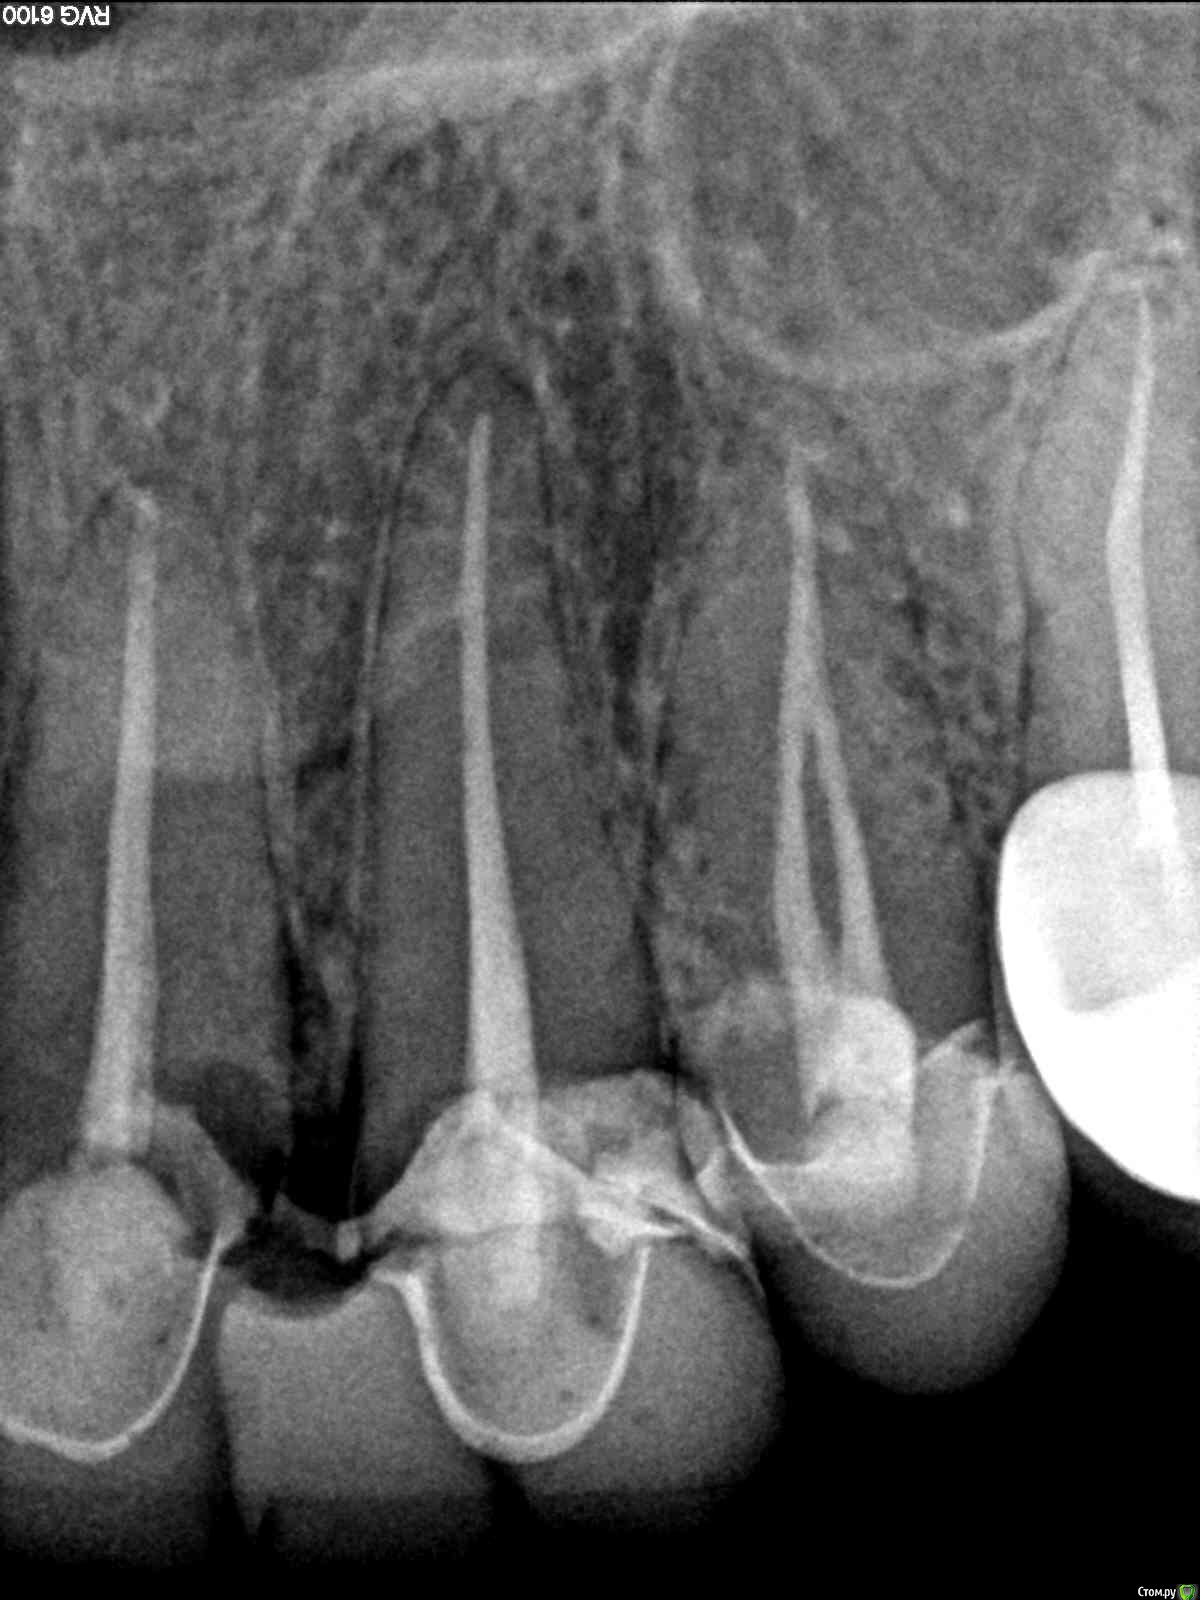

помогите пожалуйста определиться с конструкцией на фронт. обломились до уровня десны 11 и 13 зубы (на фото 1 и 2). на них стоял безмет мост с замещением 2-к. можно ли в такие условия - у десен виден кариес корня, хотя на самих корнях воспаления нет, запломбированы хорошо до верхушки, поставить кхс вкладки и повесить на них мост. если да - то какой материал выбрать для этого моста, чтобы конструкция выглядела эстетично и простояла 6-9 мес.  (до момента удаления фронтальных зубов и замещения их имплантами. ) удалить эти корешки я сейчас не могу, т.к. они "держат кость" для последующей одномоментной имплантации. ортопед в районной поликлинике предложил поставить вкладки, в те условия что есть, разработал канал под вкладки, снял слепки для вкладок, и запечатал зубы. но я вижу черные ободки кариеса вокруг запечатанных каналов. счищать по всей видимости мне его не будут, или это не возможно. мне в принципе пофигу, что там будет с небной стороны, чернота, так чернота. главное чтоб фасад был закрыт, эстетичен, не заболел и простоял минимум пол года.

посмотрите пожалуйста снимок и фото внутриротовое. так делать можно?